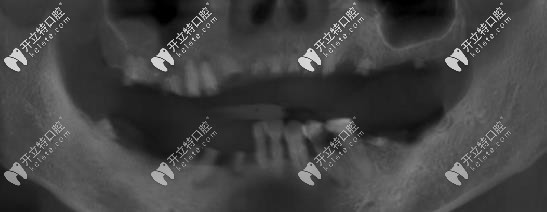

曲面斷層片

口腔情況:上半口牙全掉,下半口有5顆松動牙,牙位已變動,曾帶過一段時間的活動義齒。